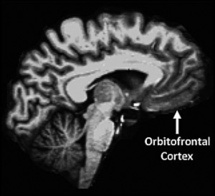

La corteza orbitofrontal, que forma parte de la región prefrontal y está implicada en los procesamientos socio/emocionales, mostró asociaciones similares con la personaldiad. Fuente: Universidad de Washington.